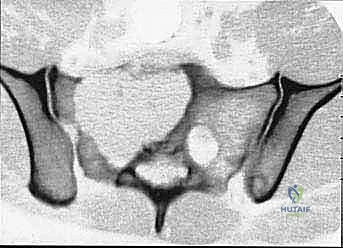

- Plain Radiography (FIG 2): While of limited value for early lesions, it provides an initial overview. As you can see in Figure 2A, we have a large lytic lesion of the right periacetabular region. Figure 2C shows a cartilage-forming lesion in the left ilium. However, plain films often underestimate the true extent of these tumors.

* CT with Intravenous Contrast and 3D Reconstruction (FIG 3): This is our workhorse for assessing bone involvement, destruction, and the critical relationship between the tumor and major pelvic blood vessels. It reveals any distortion of the pelvic anatomy and guides resectability. Figure 3A clearly shows extensive bone destruction and tumor extension into the pelvis and gluteal region. Figure 3C highlights an extensive tumor on the medial aspect of the ilium with destruction of the inner table.